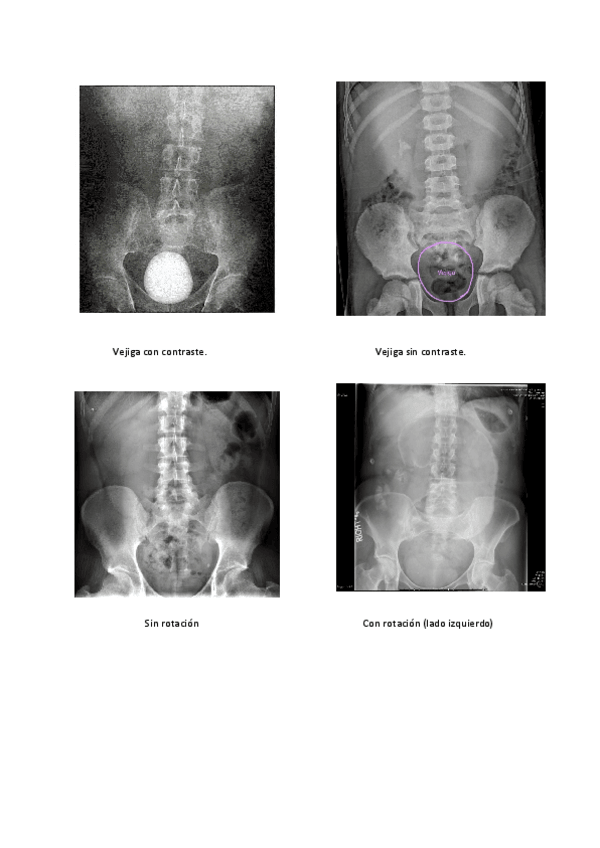

He publicado nuevos apuntes de Técnicas de Radiología Simple: Cuaderno-de-fotos-radiograficas.pdf

14 páginas

He publicado nuevos apuntes de Técnicas de Radiología Simple: Cuaderno-abdomen-HLC.pdf

3 páginas